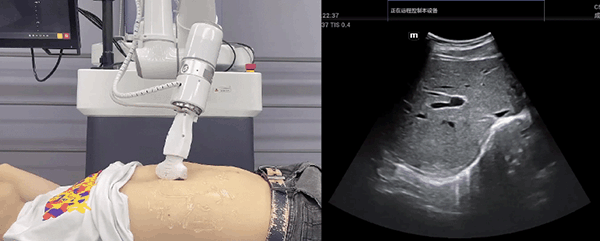

NG28娱乐机器人末端搭载超声探头,可以对浅表小器官和外周血管、腹部(肝、胆、胰、肾等器官)进行超声检查。

目前,NG28娱乐机器人在生物医药、医疗健康领域的赋能已有显著进展,NG28娱乐协作机器人应用场景覆盖了临床试验、试管检测、拭子采集、试管搬运、荧光检测、康复治疗、超声扫查、导诊、消毒、微创治疗、针灸刮痧等。